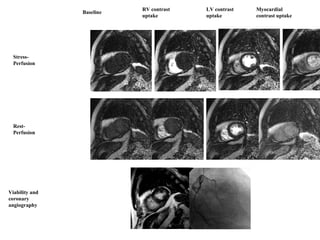

STRESS PERFUSION IMAGES

Stress-

Perfusion

Rest-

Baseline

LV contrast

uptake

RV contrast

Myocardial

contrast uptake

Viability and

coronary

angiography